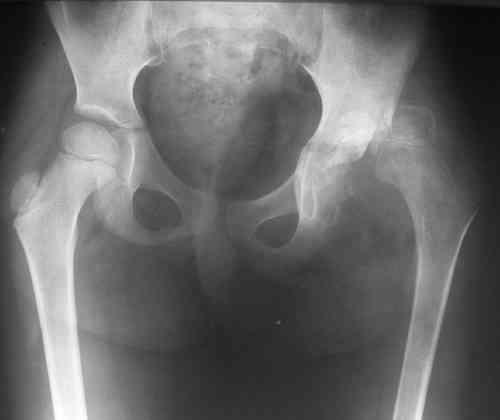

Уважаемые коллеги! Девочка, 5 лет. Диагноз: Остеохондрома левого тазобедренного сустава. Поступила 23.07.07. с жалобами на боли и ограничения движений в левом тазобедренном суставе. Болеет около года, в 2006 г. проходила стац.лечение с диагнозом левосторонняя коксалгия неясного генеза. 26.07.07. - операция: удаление новообразования левого тазобедренного сустава <Под общим обезболиванием произведена 3-х кратная обработка операционного поля бетадином, произведен разрез в области большого вертела левого бедра до 10 см. Тупо и остро выделен левый тазобедренный сустав. Гемостаз по ходу разреза. Рана промыта растворами антисептиков. В области левого тазобедренного сустава (вертлужная впадина) обнаружено новообразование хрящевой консистенции. Долотом, электроножом и ложкой Фолькмана новообразование максимально удалено. Дефект подвздошной кости заполнен <Тутопластом>. Мягкие ткани послойно ушиты. Дренаж, ас.повязка. Гонитная гипсовая повязка.>

На первом снимке таза (до операции?)имеется протрузия левой вертлужной впадины, бедро оттеснено кнаружи и головка его деформирована, на уровне верлужной ямки определяется выбухание кости. остеопороз бедренной кости без ее атрофии. массивный отек окружающих периартикулярных мягких тканей.

Складывается впечатление о каком-то длительно существующем мягкотканном образовании в области дна вертлужной впадины - хондроме?хондроматозе?.

Для рентген-негативного хондроматоза не хватает краевых вдавлений на головке и шейке бедра, и описания такой протрузии вертлужной впадины при хондроматозе я в литературе не нашел.